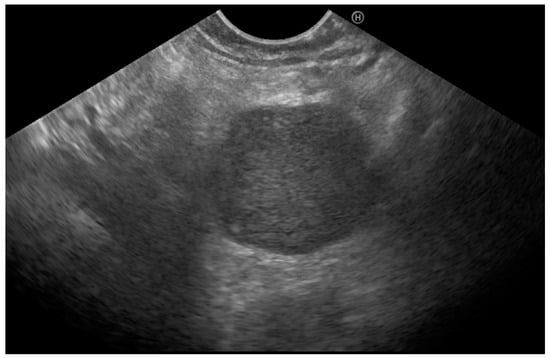

A 68-year-old dialysis patient presented for further evaluation of a pancreatic mass detected on ultrasound and confirmed by CT scan. He was complaining of postprandial bloating but had overall good performance status. Three years before the presentation, the patient had undergone right nephrectomy for Grawitz tumor and was currently undergoing dialysis. Laboratory workup showed considerably decreased glomerular filtration rate and mild normocytic anemia, with no other specific findings. Tumor markers (CEA, CA 19-9, CA 125) were within normal limits. EUS revealed a 25 mm cephalopancreatic mass (Figure 3) with a hard homogeneous pattern on elastography and a hyperenhancing pattern on contrast administration (SonoVue). Transduodenal FNB with a 20G needle confirmed the mass to be an RCC metastatic lesion. The patient was started on sunitinib treatment. The patient did not show disease progression at the 2-year follow-up.

Endoscopic ultrasound using a linear probe positioned in the duodenum, showing a hypoechoic round mass in the head of the pancreas.